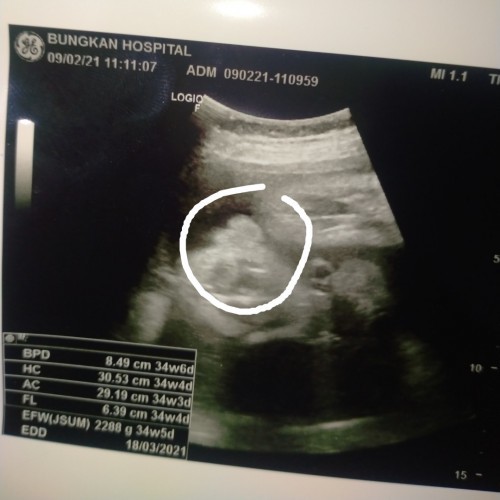

หมอบอกจิมิค่า😂😂 ตอนนี้34+4แล้ว